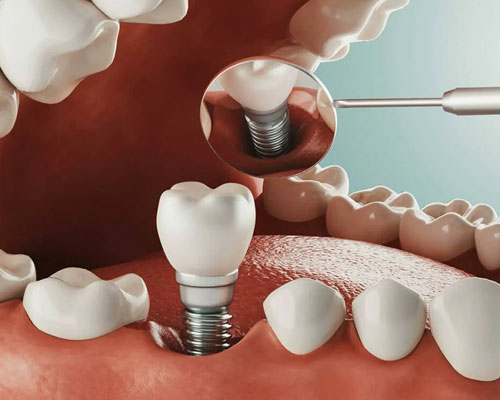

15000+

Successful Cosmetic and

Implant Cases

With more than 10000 successful cosmetic and implant cases over a decade has defined us as one of the best Dental Clinics in Mira Road.

With more than 10000 successful cosmetic and implant cases over a decade has defined us as one of the best Dental Clinics in Mira Road.

We have completed more than 10000 Successful Cosmetic and Implant Cases